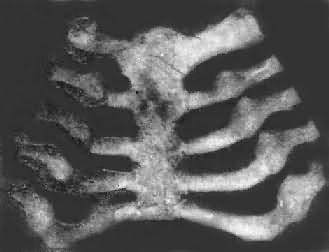

图17-10 骨骺线不整齐、变宽、软骨呈舌状向骨干伸展 (2)颅骨及肋骨:在婴幼儿颅骨的病变常很明显,常在佝偻病的早期即可出现。颅骨骨缝及囟门闭合常延迟或不完全,因此头形常较大,囟门部呈结缔组织性膜样结构。此外,由于额骨前面的两个骨化中心和顶骨的两个骨化中心都在膜内骨化过程中发生钙化障碍,因此类骨组织在颅骨的四角堆积并向表面隆起,形成方形颅。颅骨由于骨化停止,严重者骨质菲薄,批压时凹陷,并有如乒乓球样的弹性感。 肋骨和肋软骨结合处的改变与长骨骺板及干骺端的改变相似,由于软骨及骨样组织的堆积,致使肋骨和肋软骨的结合部呈结节状隆起。因多个肋骨同时受累,故结节状隆起排列成行,形似串珠,称为佝偻病串珠(rachitic rosary)(图17-11),常是佝偻病的较早期表现之一。此外,肋骨因含钙量少,缺乏韧性,同时由于膈在呼吸时的长期牵拉,在胸壁前部左右两侧各形成横行的沟形凹陷,称为Harrison沟。又因在呼吸时,肋骨受肋间肌的牵拉而下陷,使胸骨相对向前突出,形成鸡胸畸形。

图17-11 佝偻病的肋骨 肋骨和肋软骨结合部呈结节状隆起,排列成行,形似串珠 除上述常见的佝偻病改变外,还有两种较少见的佝偻病,即①先天性或胎儿性佝偻病,在婴儿出生时已有佝偻病表现,主要是由于母亲在怀孕时有严重的维生素缺乏所致。②晚期佝偻病,多见于北方地区,发病多在10岁以后的儿童,故其改变介乎婴幼儿佝偻病和骨软化症之间。因此时颅骨的骨化已基本完成,而肋骨生长较慢,故方形颅和肋骨串珠等均不显著。骨骼生长较慢,严重时可形成侏儒畸形。 2.骨软化症病理变化骨软化症发生于成人,其改变与佝偻病相似。因成人的骨发育已停止,故其改变限于膜性化骨的钙化障碍,致过量的类骨组织堆积在骨的表面,骨质变软,同时因为承重力减弱而导致各种畸形,常见的有骨盆畸形,脊柱侧突及长骨弯曲等。骨盆畸形表现为骨盆的前后径及左右径均变短,耻骨联合处变尖而向前突出,呈鸟喙状,称为喙状骨盆。